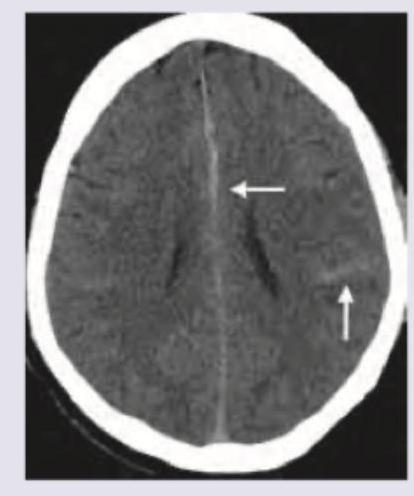

What is the correct diagnosis based on the image shown below?

Explanation: ***Dense MCA sign*** - The image displays a hyperdense (bright) appearance of the **Middle Cerebral Artery (MCA)**, particularly noticeble in the Sylvian fissure on the left side (indicated by the shorter arrow). This is highly suggestive of a **thrombus within the MCA lumen**, one of the earliest signs of an acute ischemic stroke on non-contrast CT [1]. - This finding is a strong indicator of **large vessel occlusion** and is crucial for guiding acute stroke management, such as the administration of thrombolytics or mechanical thrombectomy [1]. *Lacunar stroke* - Lacunar strokes are typically **small, deep infarcts** caused by occlusion of small penetrating arteries, which are not directly visible as a hyperdense vessel sign on non-contrast CT [3]. - The image shows a larger-scale vascular finding, not a small, isolated infarct characteristic of a lacunar stroke [3]. *Subarachnoid hemorrhage* - Subarachnoid hemorrhage (SAH) appears as **high-density blood** filling the subarachnoid spaces, fissures, and sulci [2]. - While the image shows some hyperdensity, it is specifically confined to a major arterial structure (MCA), not diffuse within the subarachnoid space as seen in SAH. *Intraventricular hemorrhage* - Intraventricular hemorrhage (IVH) is characterized by **hyperdense blood within the ventricular system** of the brain [2]. - The image does not show blood within the ventricles; the hyperdensity is clearly located along the course of a major cerebral artery. **References:** [1] Kumar V, Abbas AK, et al.. Robbins and Cotran Pathologic Basis of Disease. 9th ed. The Central Nervous System, pp. 1266-1268. [2] Cross SS. Underwood's Pathology: A Clinical Approach. 6th ed. Common Clinical Manifestations Of Central And Peripheral Nervous System Disease, pp. 706-707. [3] Kumar V, Abbas AK, et al.. Robbins and Cotran Pathologic Basis of Disease. 9th ed. The Central Nervous System, pp. 1269-1270.